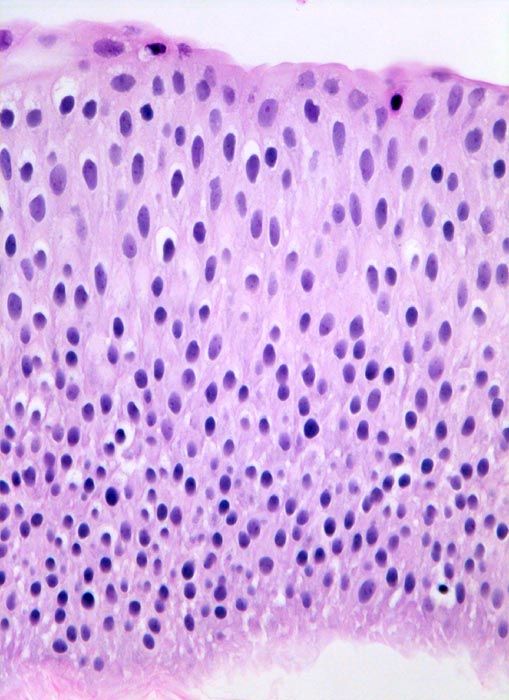

n/ Papilläres Urothelkarzinom pTa, G1 + G2

Papilläres Urothelkarzinom pTa, G1 + G2

Bei den meisten papillären Urotheltumoren finden sich kleine Büschel von kubischen oder zylindrischen Urothelien. Die Kerne sind leicht vergrössert, oft spindelig und hyperchromatisch. Papilläre Karzinome mit leichter Epitheldysplasie sind aufgrund der sehr geringen Zellatypien in bis zu 50% der Fälle zytologisch nicht diagnostizierbar. Bei mässiger Epitheldysplasie sind die Urothelien polymorpher und hyperchromatischer.

Unten werden Beispiele von einem hoch differenzierten und drei mässig differenzierten papillären Karzinomen gezeigt.